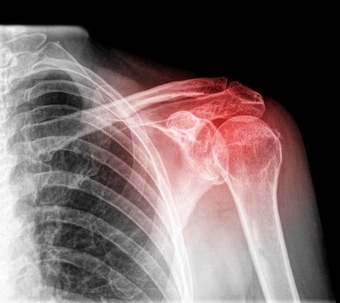

Xray of a shoulder injury

Shoulder injuries often occur on the job from a fall or from lifting. Severe shoulder injuries can require surgery. Of course, workers' compensation carriers frequently deny or delay shoulder surgeries to keep down expenses.